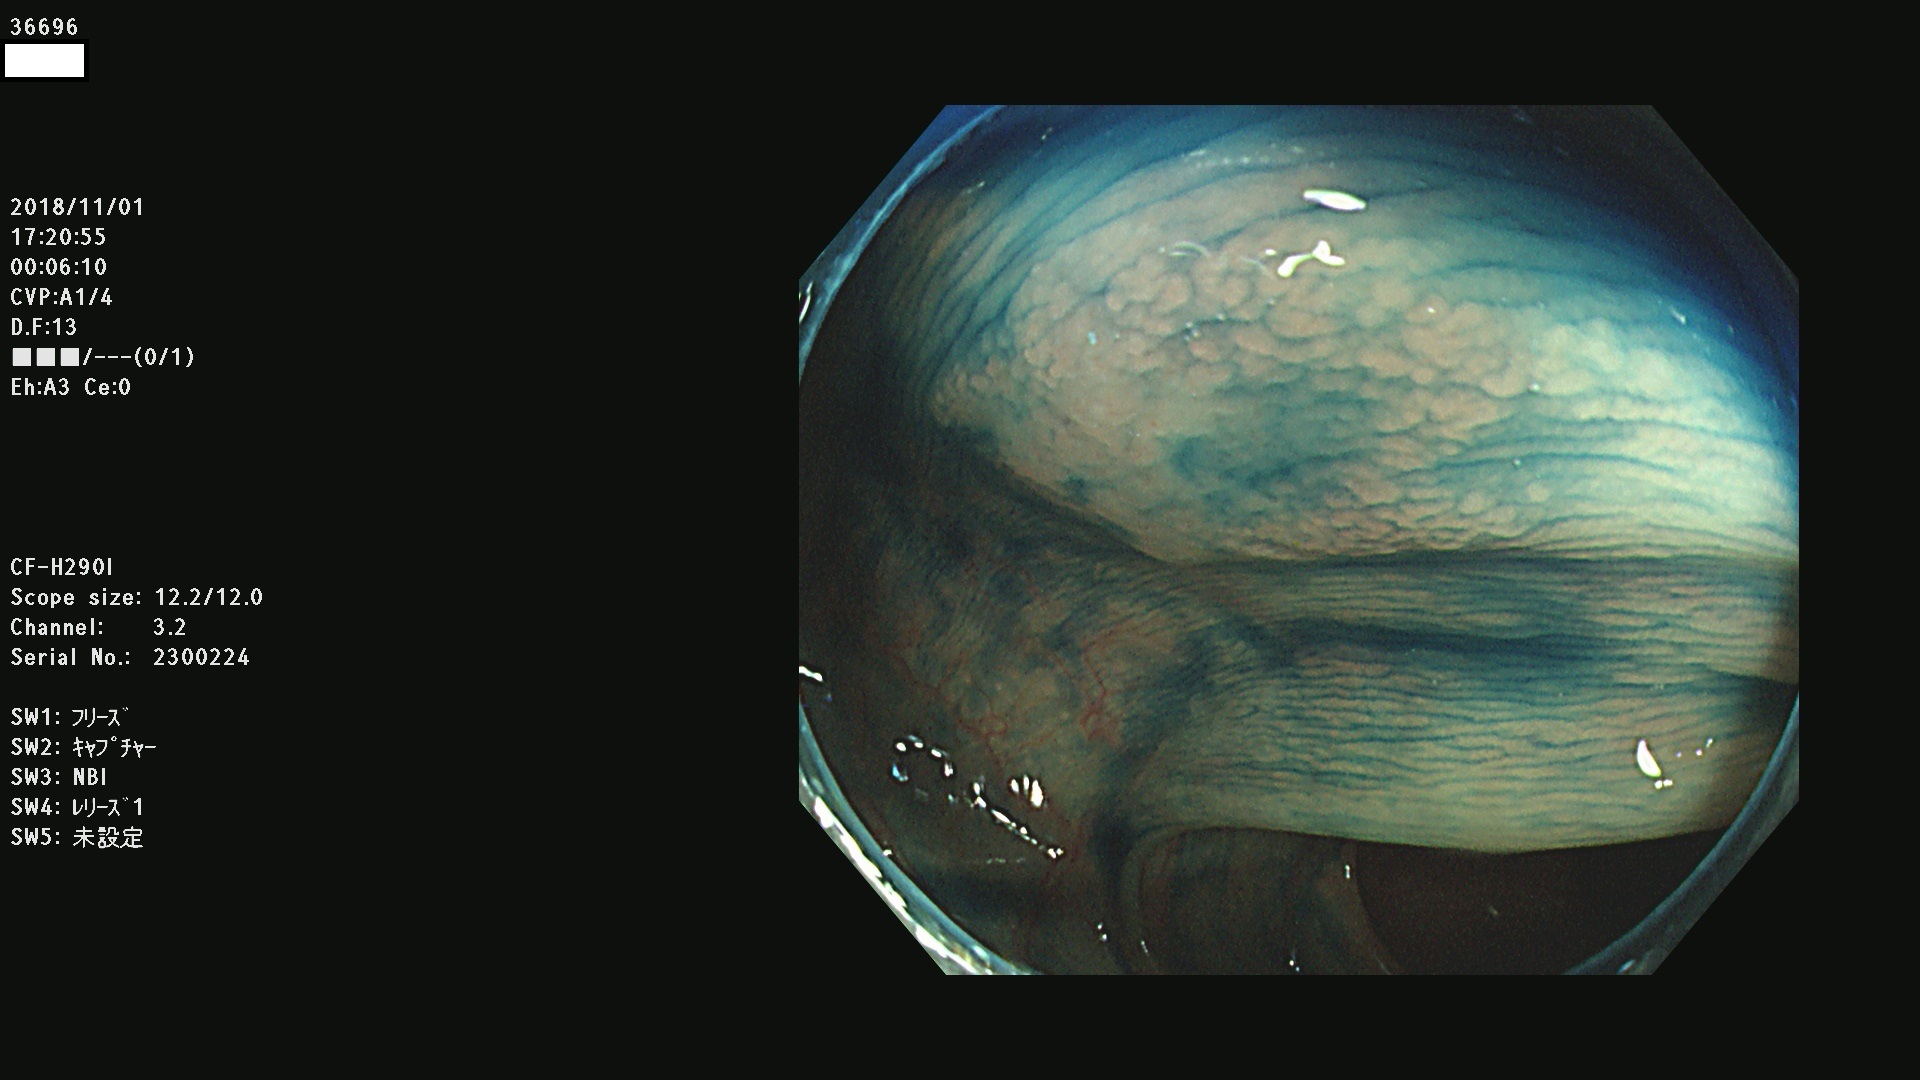

36600 36601 36603 36605 36606 36608 36609 36610 36611 36612 36613 36615 36617 36620 36621 36624 36625 36626 36627 36628 36629 36631(SSAPのみ) 36632 36633 36634 36636(SSAPのみ) 36637(SSAPのみ) 36639 36640 36642 36643 36644 36646 36647 36648 36649(SSAPのみ) 36650(SSAPのみ) 36652 36653 36654 36655(SSAPのみ) 36656 36657 36658 36659 36660 36661(SSAPのみ) 36665 36668 36669 36672 36673 36676 36677 36678 36679 36681 36682 36683 36684 36685 36687(SSAPのみ) 36691 36692 36693 36694 36695 36696 36697 36699(SSAPのみ)

発見困難で危険性の高い平坦型病変(上記100名より抽出)